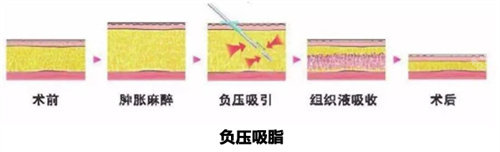

进入手术室后,麻醉师通过静脉注射进行全身麻醉,大约10分钟后我失去了意识。

醒来时已经是下午2点,双腿被厚厚的纱布包裹着,感觉像灌了铅一样沉重。

护士扶我到修养室休息,提供了冰袋和镇痛泵,虽然有轻微胀痛,但比想象中好很多。

回到酒店后,我按照医嘱将双腿抬高30度卧床休息,每小时更换一次冰袋。

凌晨时伤口开始渗液,护士提前准备的护理包派上了用场——用无菌纱布轻轻按压渗出部位,再用医用胶带固定。

这时候才体会到医院提供的加压弹力裤的重要性,虽然穿着闷热,但能有效减轻肿胀。

第二天早上拆开纱布时,我惊喜地发现腿围已经减少了3厘米,虽然还很肿,但轮廓明显变流畅了。